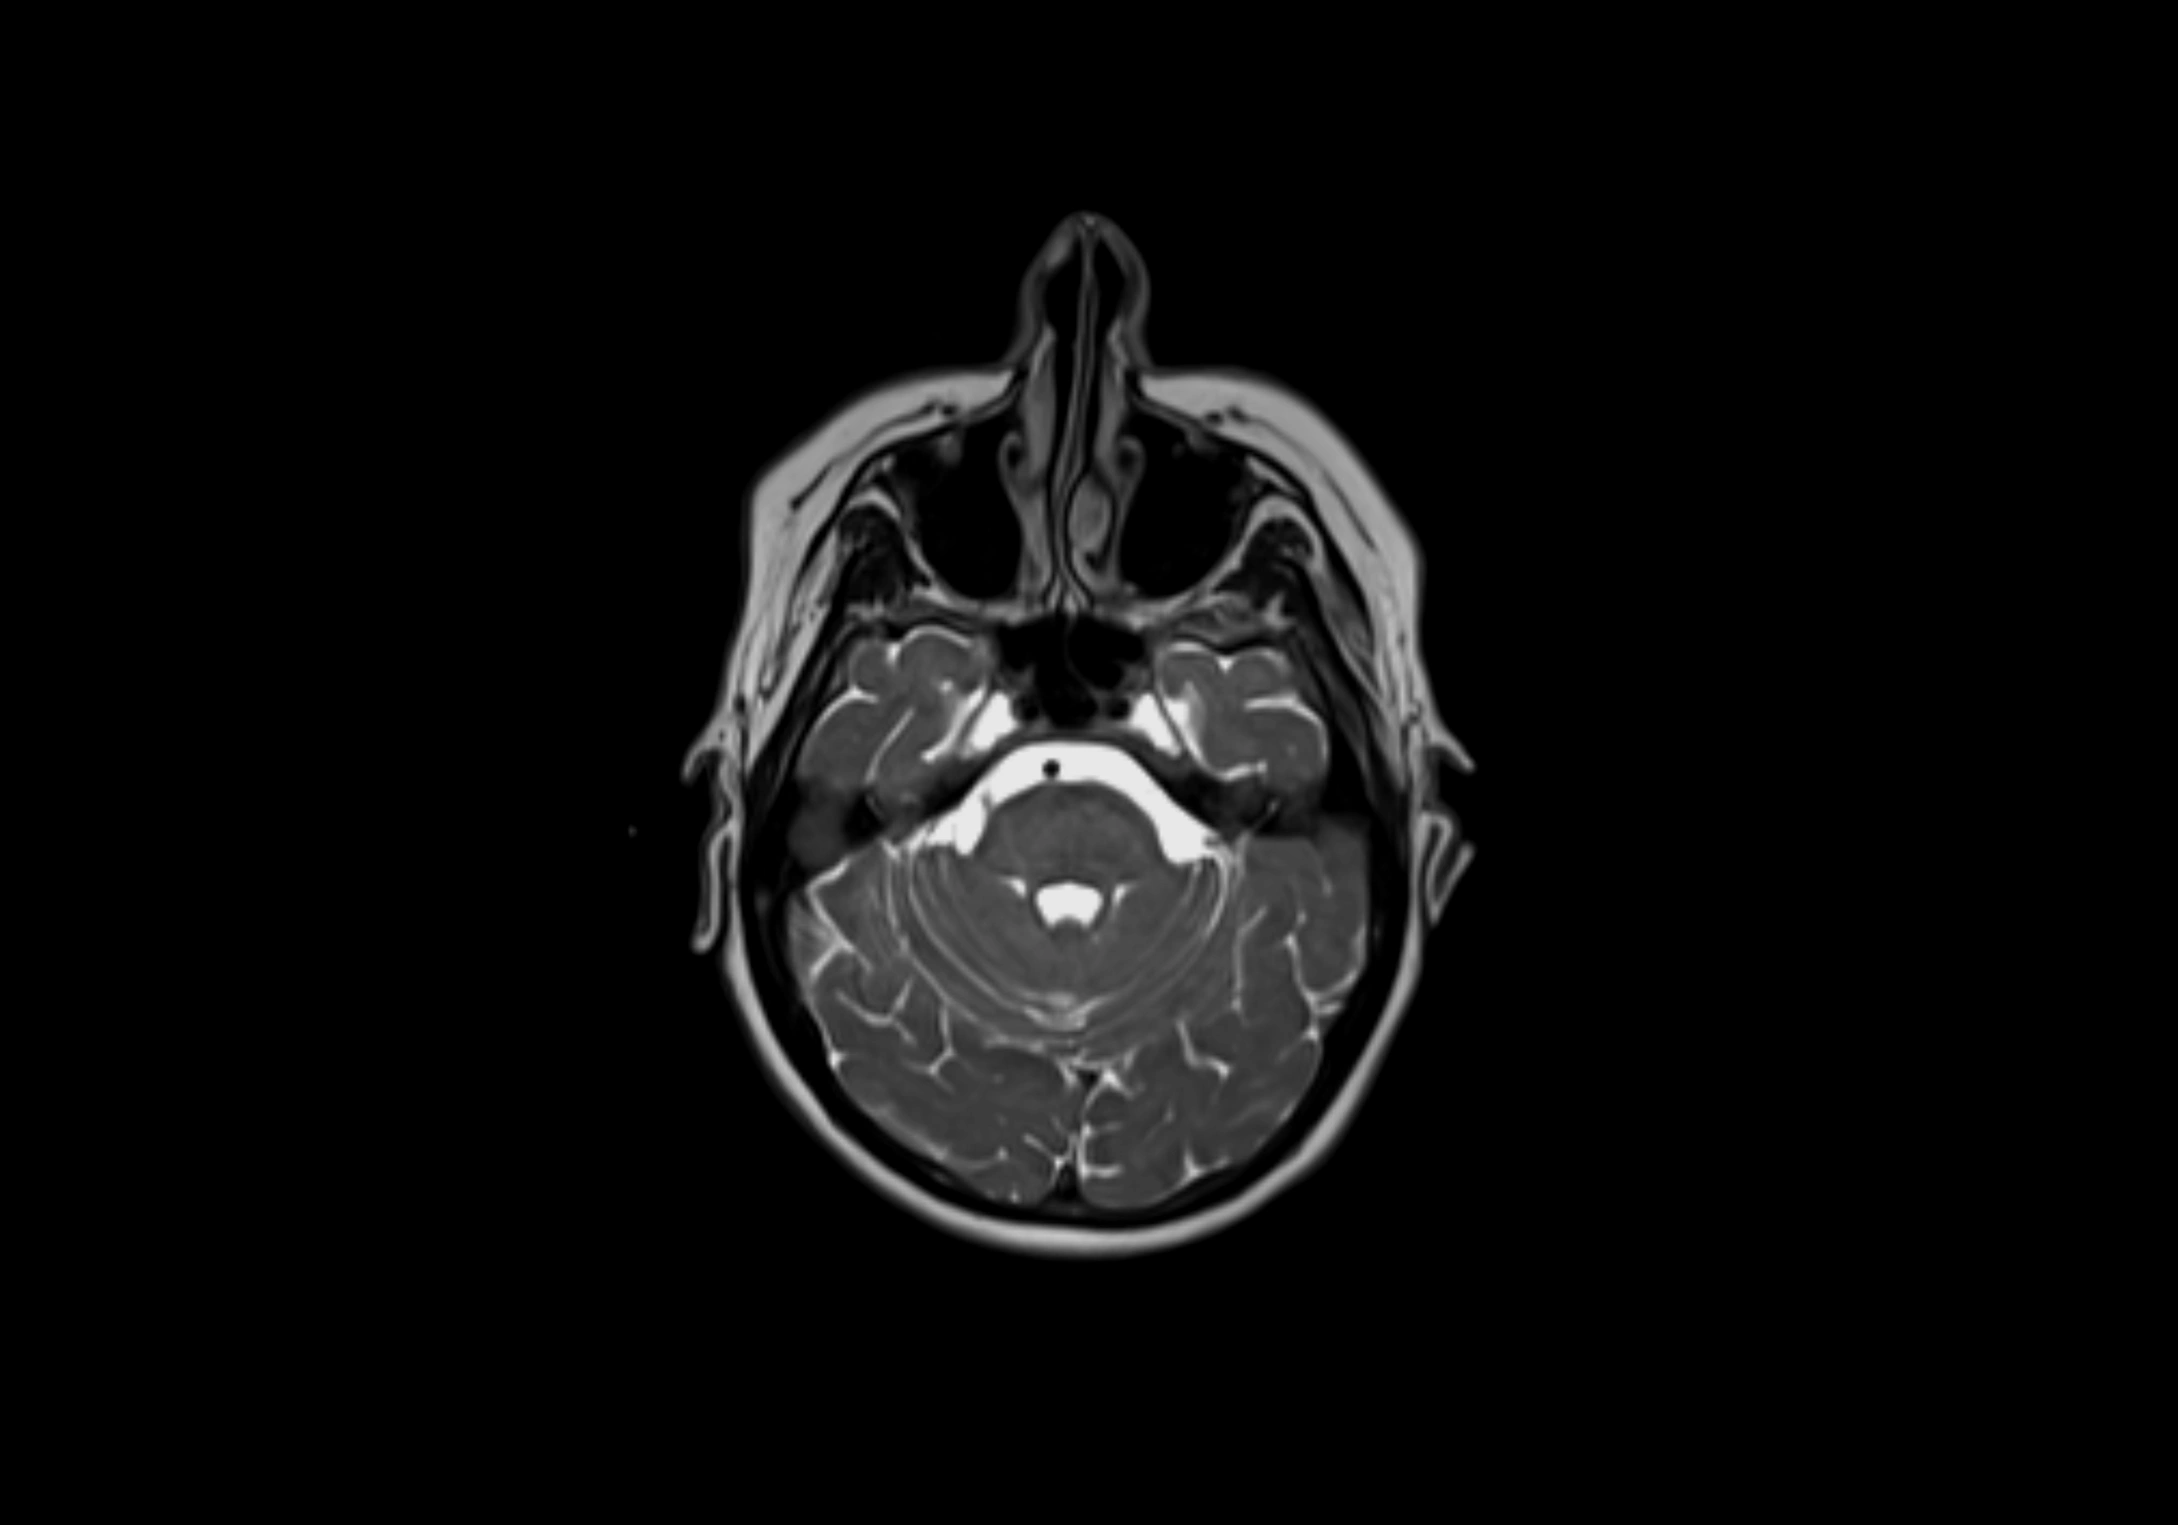

MRI Appearance

T2-weighted images:

• Nodes show intermediate signal, with surrounding fat bright

• Useful for detecting edema, inflammation, or infiltration

• Fatty hilum may appear slightly hyperintense relative to cortex

MRI images

image